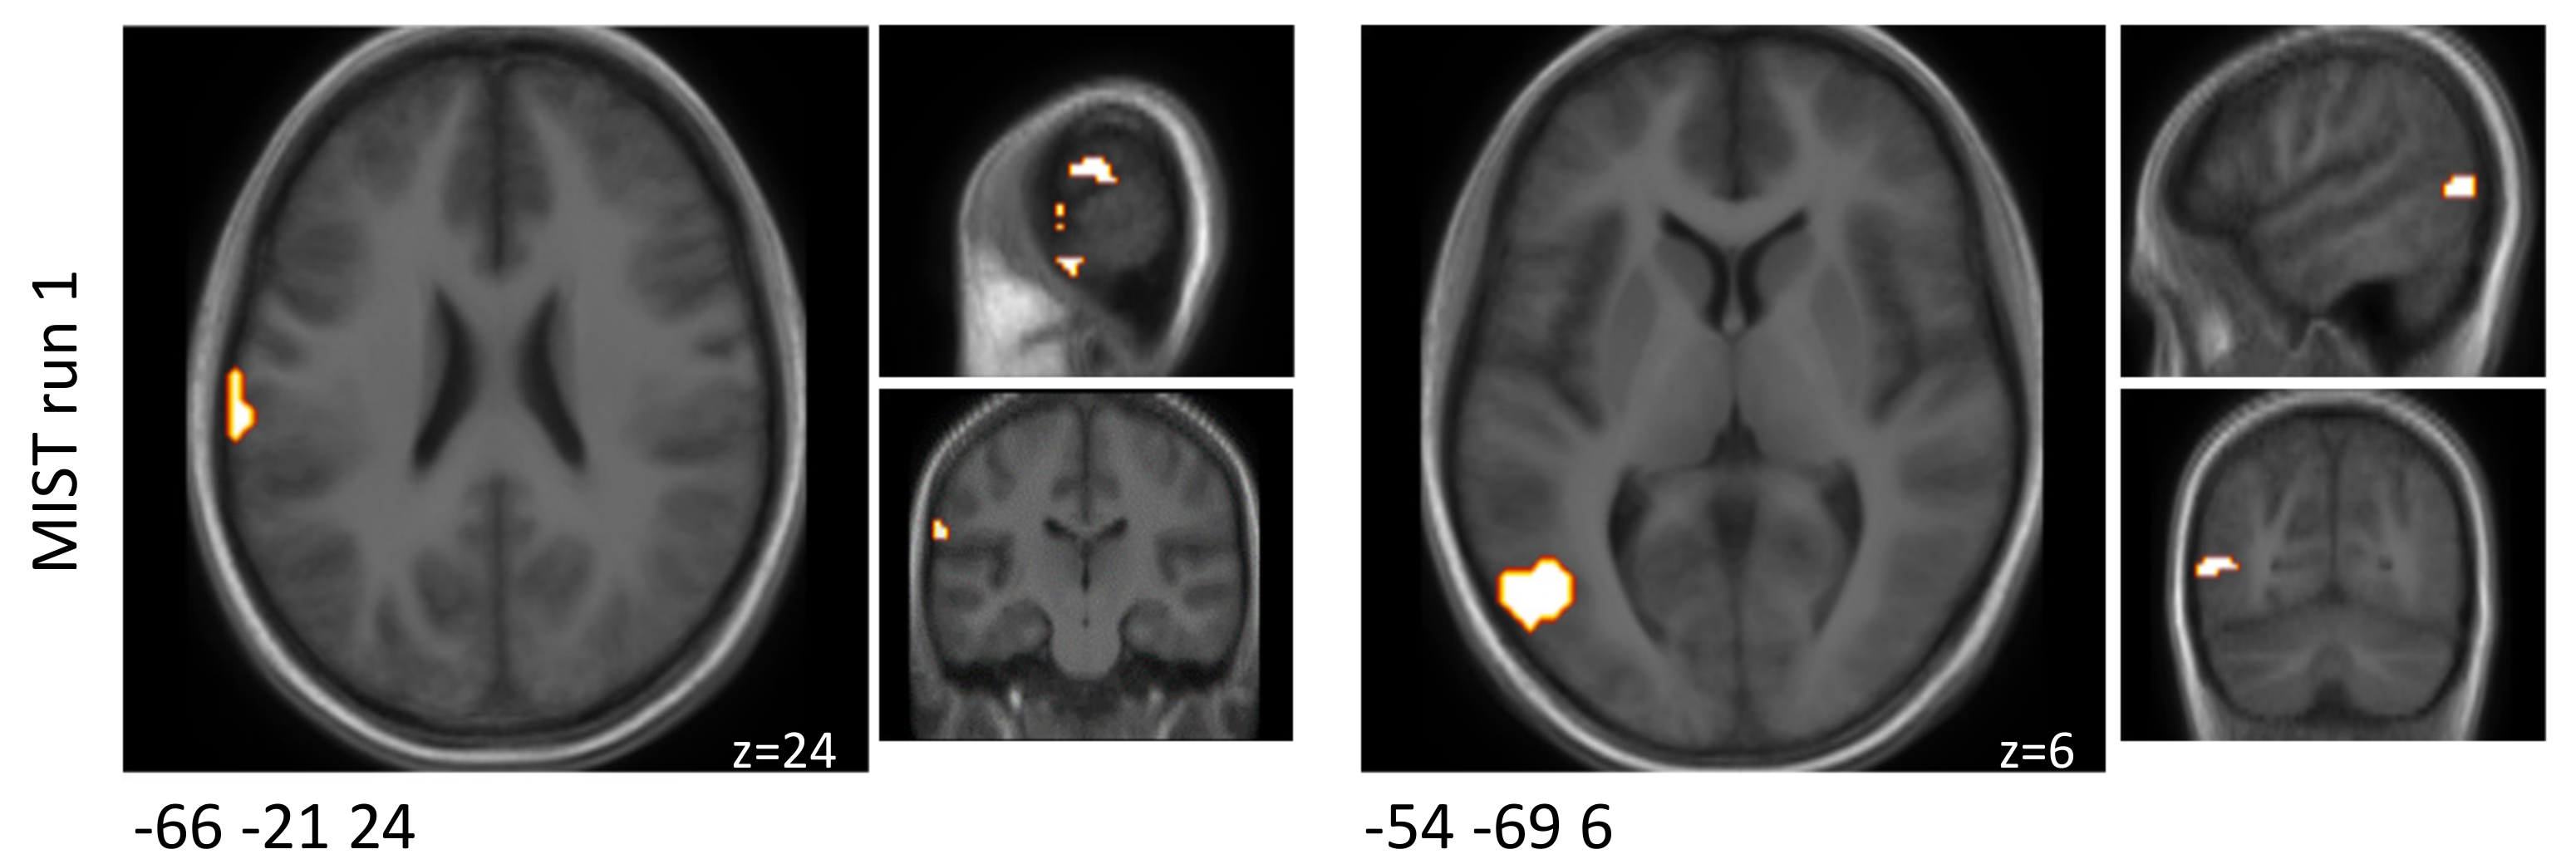

In MIST run one, functional connectivity between two of these clusters was found to be significantly (FDR-corrected p = 0.02) increased by the probiotic intervention (Table 3 and Figure 3). These two clusters were located in the upper limbic and medioventral regions; the latter was among the predefined ROIs. During the MIST runs two and three, no alterations in functional connectivity were observed.

Figure 3. Schematic visualisation of clusters that were found to be associated with significant (FDR-corrected p < 0.05) functional connectivity changes when comparing the probiotic and the placebo interventions (probiotic > placebo) during the MIST paradigm. One of these clusters covered a predefined ROI (italic). Clusters are superimposed on average anatomical scans. Clusters can be identified by the coordinates of their peak (x y z).

Table 3. Clusters that were found to be associated with significant functional connectivity changes between both interventions during the MIST paradigm. One of these clusters covered a predefined ROI (italic).

MNI Coordinates of Peak (x y z)Cluster Size [mm3]Anatomical RegionMNI Coordinates of Peak (x y z)Cluster Size [mm3]Anatomical RegionT

Probiotic-Placebo

FDR

MIST run 1

36 −15 42297A4ul, area 4 (upper limb region)−33 −78 −18405A37mv, medioventral area373.60.021

MIST run 2

none

MIST run 3

FDR—False discovery rate, MIST—Montreal Imaging Stress Task, MNI—Montreal Neurological Institute, ROI—Region of interest.